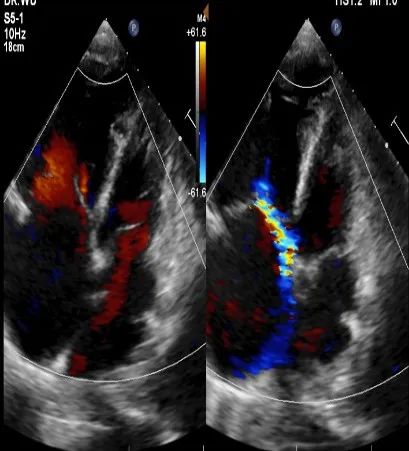

▲术前心脏彩超:右房室增大+三尖瓣、肺动脉瓣轻度关闭不全+肺动脉主干及分支增宽